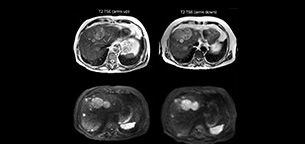

Imaging with arms up means faster, better imaging

Dr. Kukuk scans an increasing number of liver patients in an arms-up position using the integrated Posterior coil and a special positioning device. “By placing the patient’s arms up, the field of view in the right-left direction can be smaller so that a right-left preparation direction can be used to cut down the scan time,” he explains. “We can use high dS SENSE factors for TSE imaging, so we can shorten the echo train length. This results in a faster scan than arms-down T2 TSE and the images show high anatomical detail.”

“For DWI, the high dS SENSE factor allows using a shorter TE so we get higher signal and fewer susceptibility artifacts, which means less distortion of diffusion weighted images. Of course, with higher dS SENSE factors and the shortening of the TSE factor in T2-weighted imaging, we can drastically cut down the complete examination time. So, with arms-up we get faster images, less distortion in DWI and less blurring on T2-weighted images. Almost all patients tolerate the arms-up scanning well.”